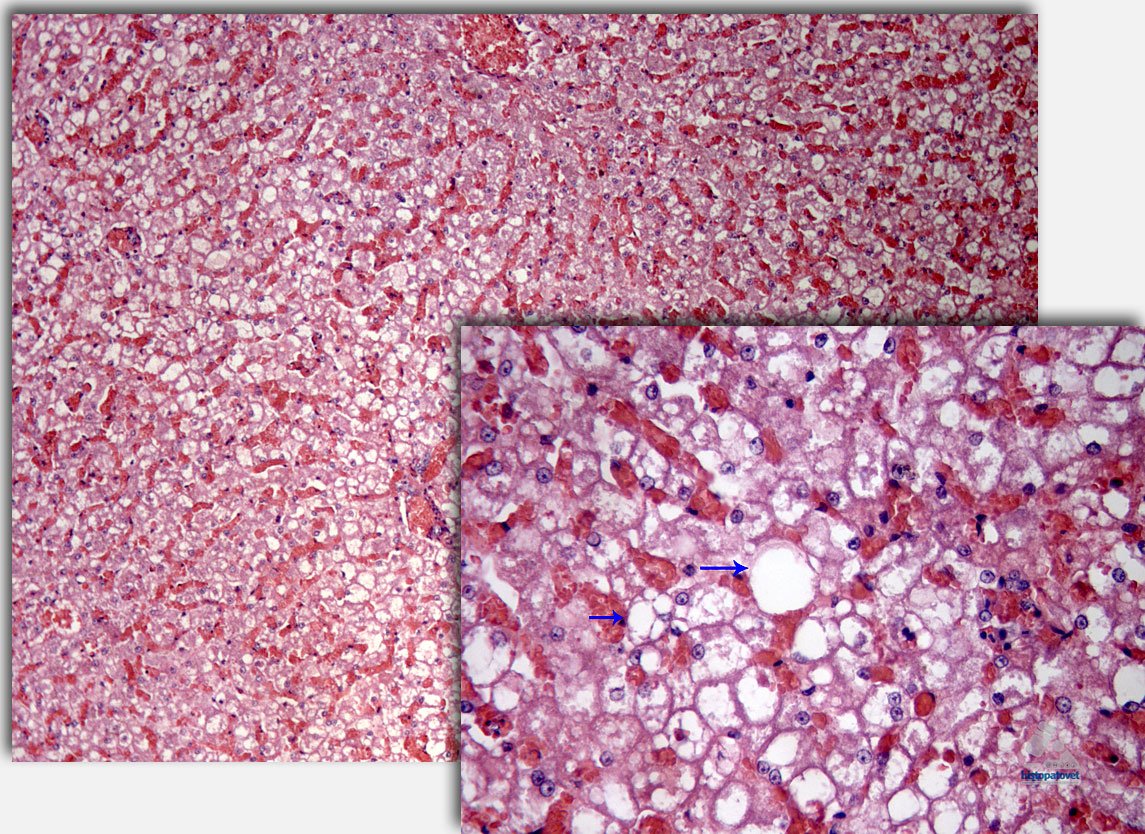

De forma difusa, los hepatocitos mostraron múltiples vacuolas vacías (lipídosis hepática). Ver las siguientes dos fotos. Las flechas muestran las vacuolas vacías.

Fig.5. De forma difusa los hepatocitos muestran las vacuolas. A la derecha un acercamiento. Causa de muerte: Insuficiencia cardio-respiratoria.